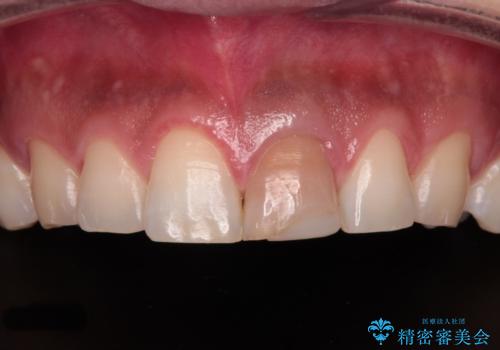

- 神経を取り除いたことで変色した前歯を気にして来院された患者様です。

根管治療はやり直さずに、ファイバーポストを使用した土台を植立してオールセラミッククラウンにて補綴することとしました。

神経を取り除いた歯は時間とともに変色してきます。

クリーニングやホワイトニングでは改善できないため、オールセラミッククラウンなどによる補綴治療が必要となります。